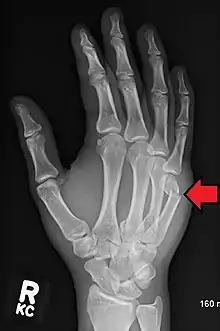

Boxer's fracture of the 5th metacarpal head from punching a wall

A boxer's fracture is the break of the 5th metacarpal bones of the hand near the knuckle.[4] Occasionally it is used to refer to fractures of the 4th metacarpal as well.[1] Symptoms include pain and a depressed knuckle.[2]

Classically, it occurs after a person hits an object with a closed fist.[3] The knuckle is then bent towards the palm of the hand.[3] Diagnosis is generally suspected based on symptoms and confirmed with X-rays.[3]

Diagnosis by a doctor's examination is the most common, often confirmed by x-rays. X-ray is used to display the fracture and the angulations of the fracture. A CT scan may be done in very rare cases to provide a more detailed picture.